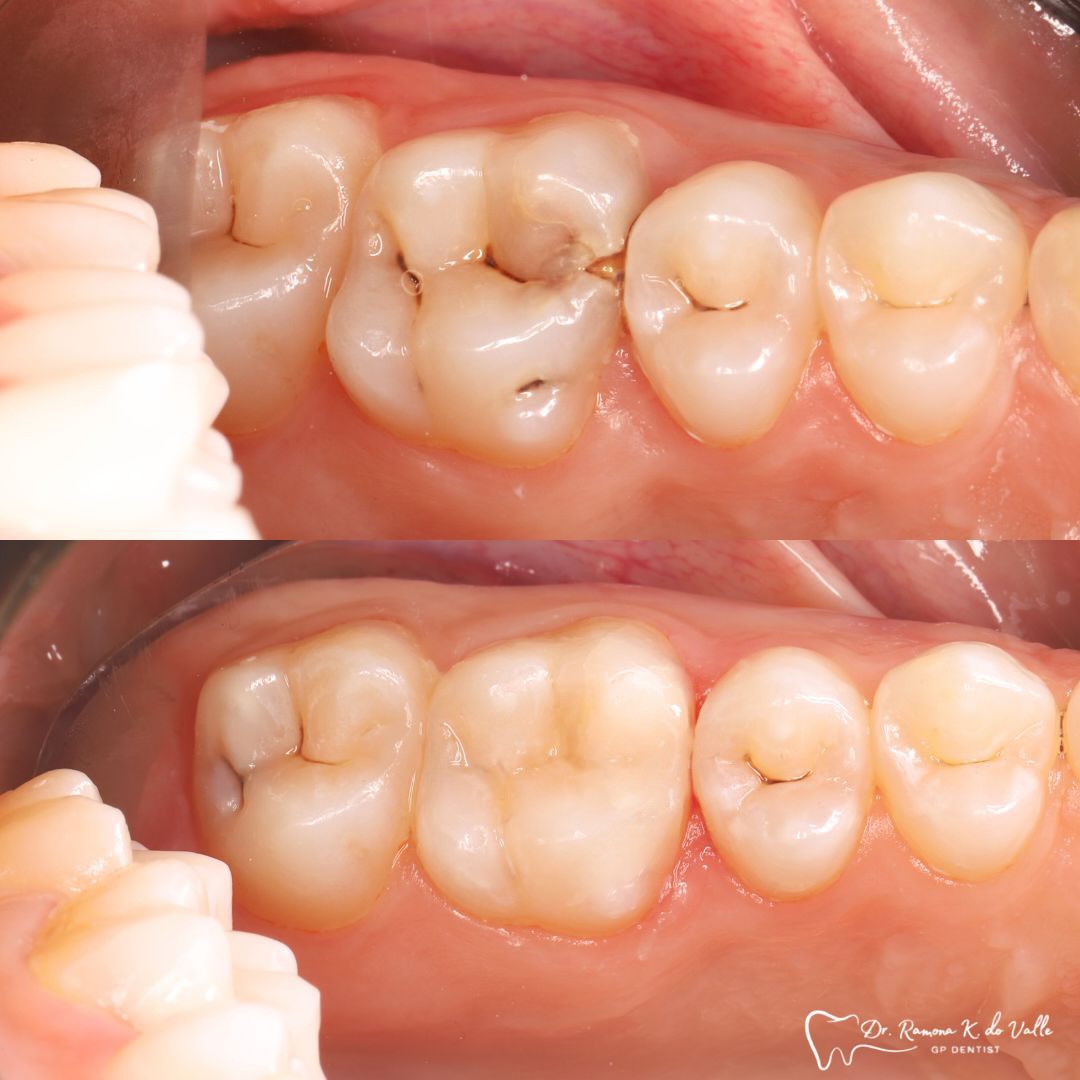

1. Preparation of the Tooth

We remove weakened or decayed tissue and clean the area thoroughly. The goal is to preserve as much healthy structure as possible.

3. Layering the Composite Resin

The tooth-coloured resin is applied in thin layers and shaped carefully to match natural anatomy. For front-tooth work, we may combine several shades for a lifelike result.

5. Final Polishing and Bite Adjustment

We contour and polish the surface to a high gloss and ensure your bite feels natural in all positions.